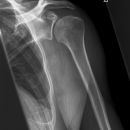

Schulter a.p. (Schultergelenk nach Grashey)

Beurteilungskriterien

- Außenrotation ->Tuberculum majus lateral randbildend, Innenrotation ->Tuberculum minus medial randbildend

- Gelenkspaltweite 4-6 mm

- Weite des subacromialen Raumes exakt nur in der 10 – 15° nach kaudal angulierten Aufnahme bestimmbar ("Morrison, Outlet View")! Normalerweise 1 - 1,5 cm, < 6 mm -> wohl pathologisch, Impingment röntgenlog. wahrscheinlich, Cave. rein klinische Diagnose!

- Normvarianten: Os glenoidale (akzessorischer Ossikel kaudal des Glenoids), persistierende Akromion- oder Korakoidapophyse, entwicklungsbedingte Pfannenranddefekte